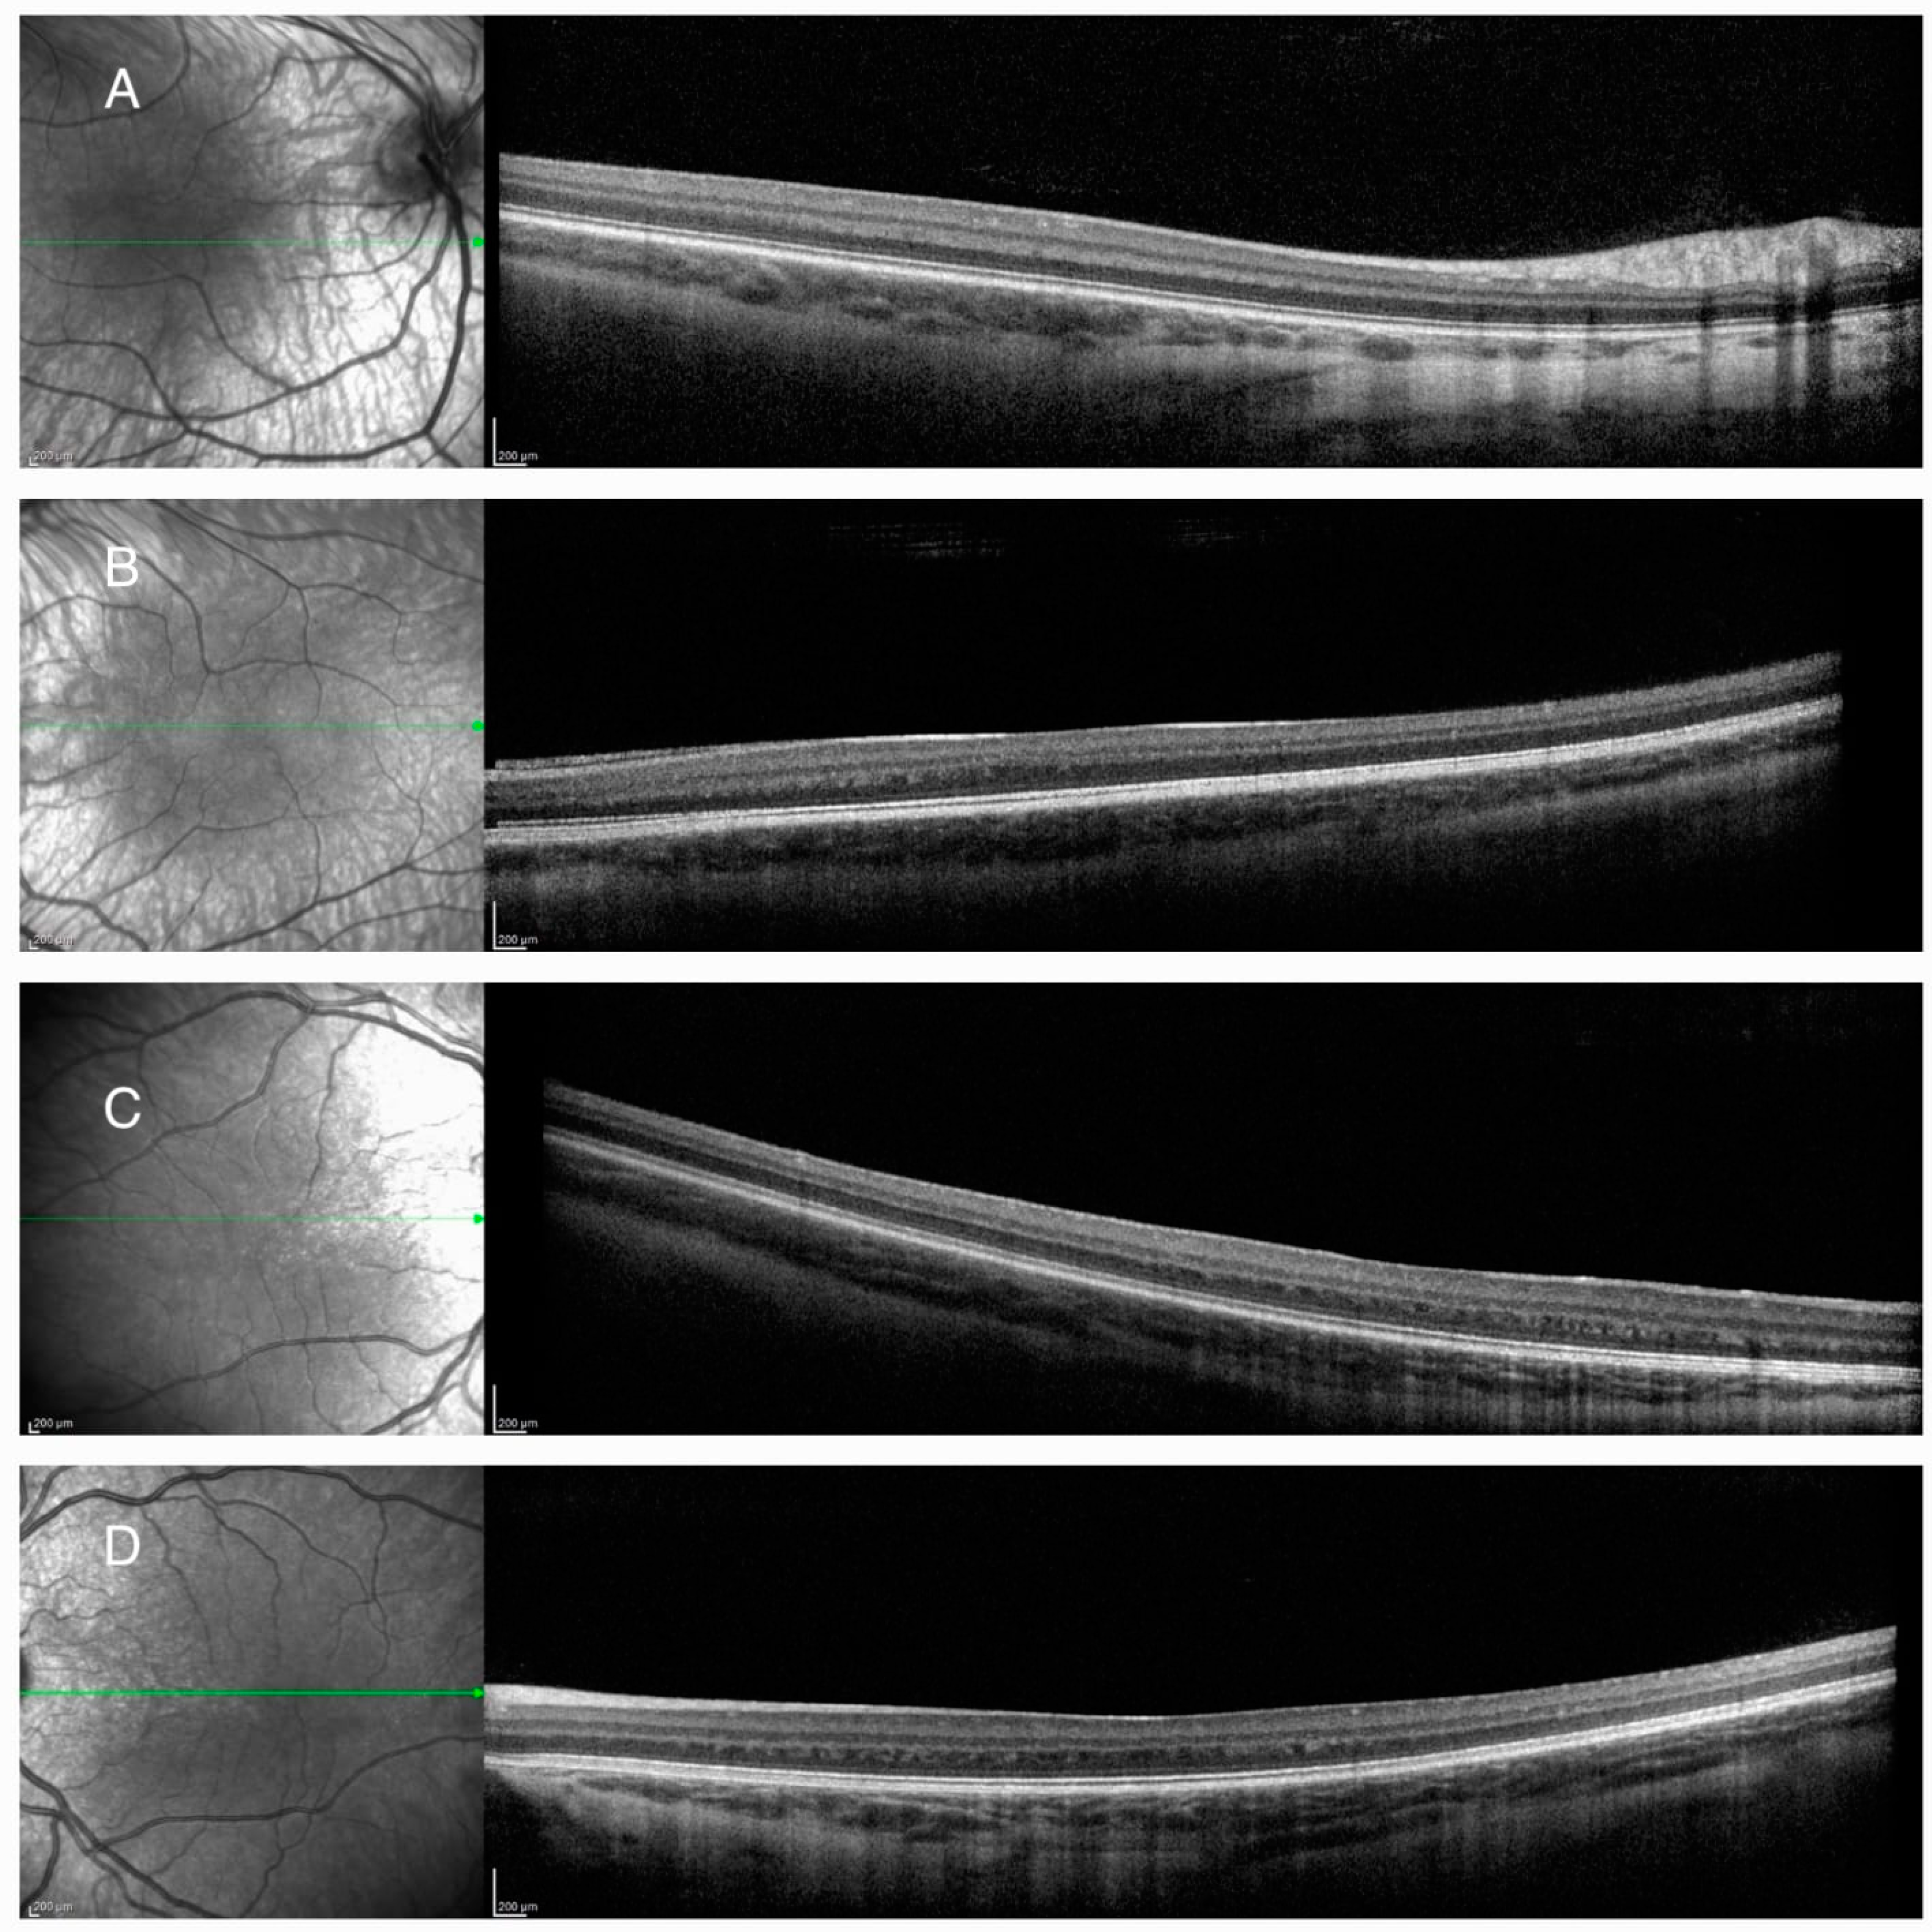

2.1. Case 1

2.2. Case 2